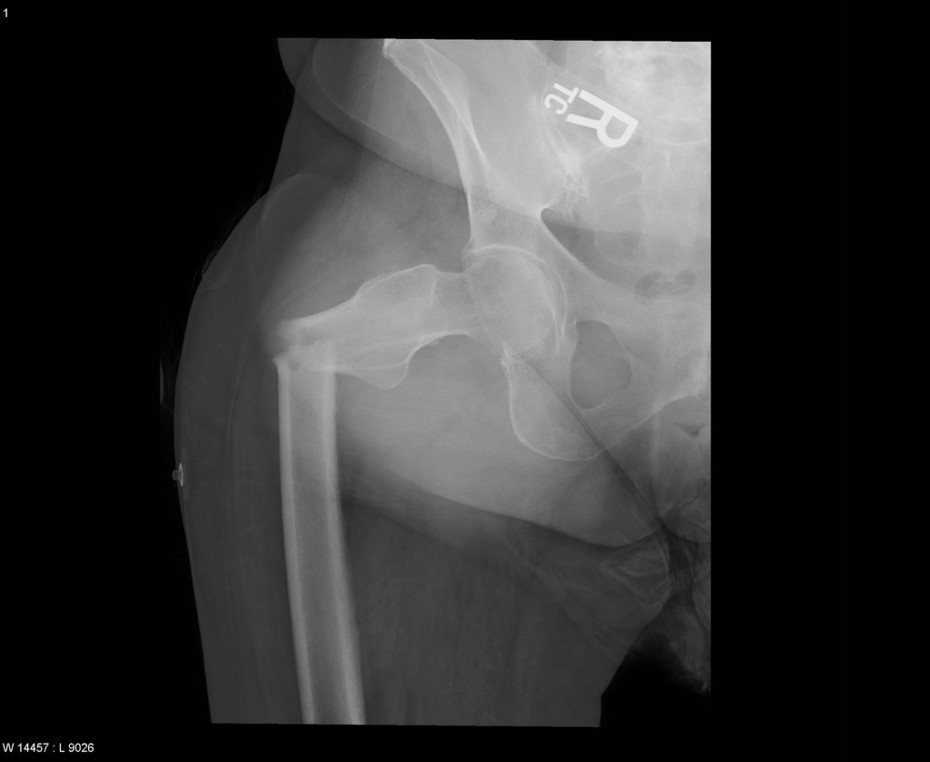

Diagnosis: Fracture of right femur with significant angulation

Modality: X-Ray

Credit: Case submitted by Dr. Landy Cohen to radRounds Radiology Network